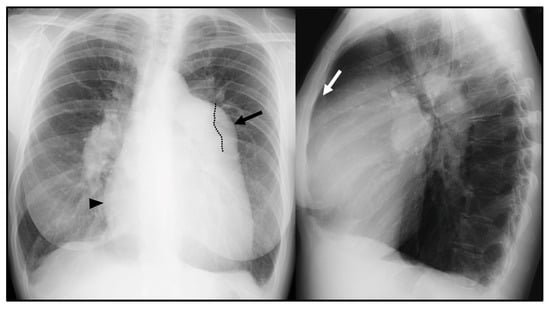

CXR is often the initial investigation in the evaluation of a patient with symptoms suggestive of PH. Even if frequently overlooked, CXR garners widespread use due to the relative ease of access, low cost [5,6], and potential capability of suggesting the presence of PH as well as the underlying cause [7]. The typical radiographic pattern of PH is characterized by the enlargement of central pulmonary arteries, associated with the tapering of the peripheral branches of pulmonary arteries, commonly referred to as pruning [7] (Figure 1). An enlarged right atrium (RA) and right ventricle (RV), commonly associated with advanced stage PH, can be evaluated on CXR as well [6]. The prominence of the right heart border (representing the RA) > 44 mm from the midline in the posteroanterior CXR and the filling of the retrosternal space in lateral film (representing RV dilation) are radiographic signs suggestive of right cardiac chamber enlargement [6]. A boot-shaped heart with an upward tilt of the cardiac apex can represent RV hypertrophy [8].

Figure 1.

Chest X-ray (CXR) signs of pulmonary hypertension: enlarged central pulmonary arteries, with the prominence of the main pulmonary artery (MPA) (black arrow); the left pulmonary artery seen within the cardiac silhouette (dotted line); tapering of peripheral pulmonary arteries (so-called pruning); prominence of the right heart border, represented by the right atrium (black arrowhead); and filling of the retrosternal space in the lateral view due to right ventricle dilation (white arrow).

CXR showed a high sensitivity (97%) and specificity (99%) in the identification of PH [9,10]; nonetheless a normal CXR does not rule out diagnosis, particularly in patients with mild PH.